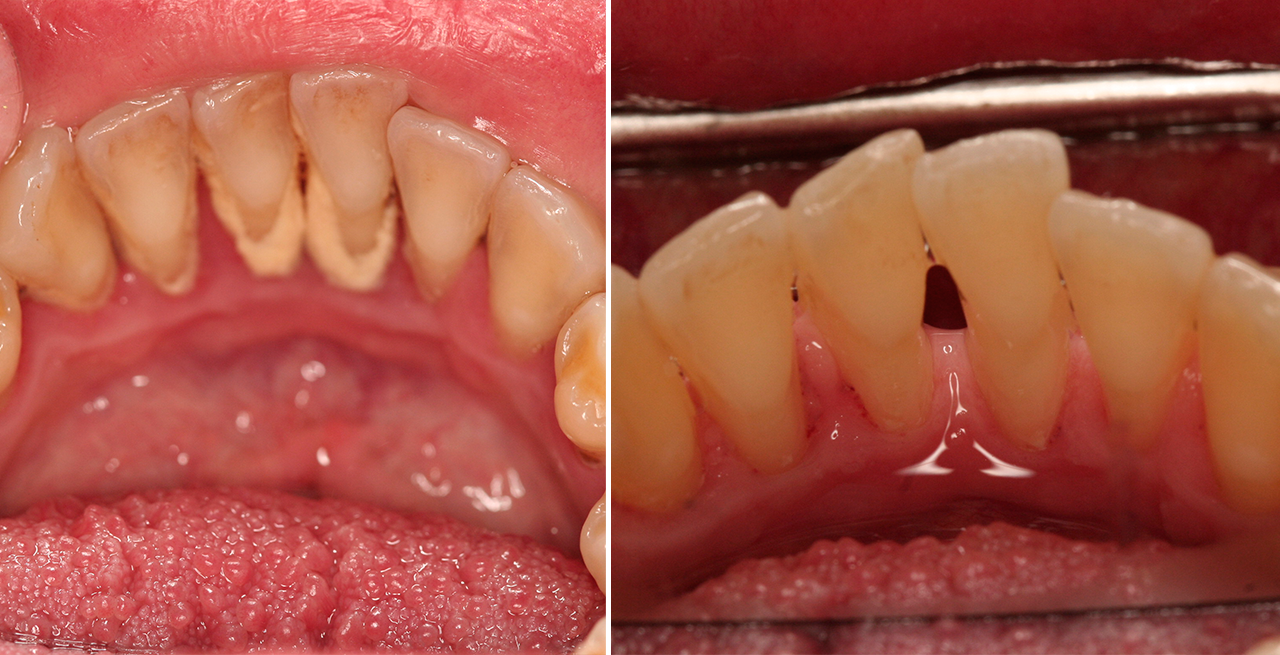

Paciente de 76 anos do sexo masculino

Motivo da consulta: Paciente desdentado total, procurava colocar dentes.